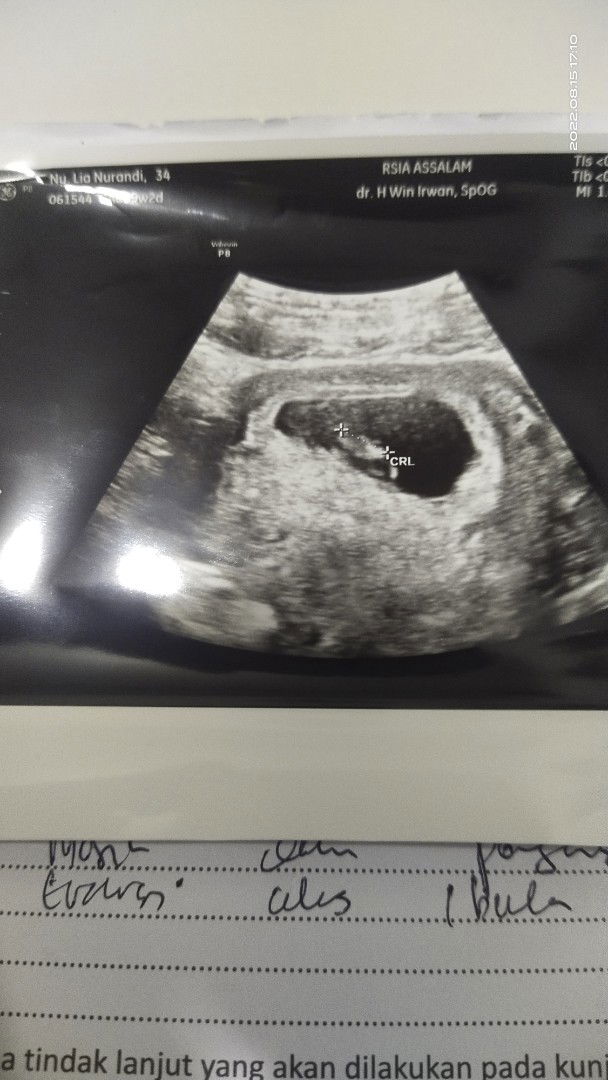

aku pernah gini, pake wc jongkok lg bab tbtb pas liat itu merah semua.. tapi aku cek di V gak keluar darah sama sekali,agak worry tp berifikir positive mungkin emg dr lubang belakang. karna emg suka gitu keluar darah pas bab karna robek atau gmn gitu kalo aku.. tp lebih baik cek usg bun atau konsul ke bidan, karna aku jg pas berapa minggu kemudian usg